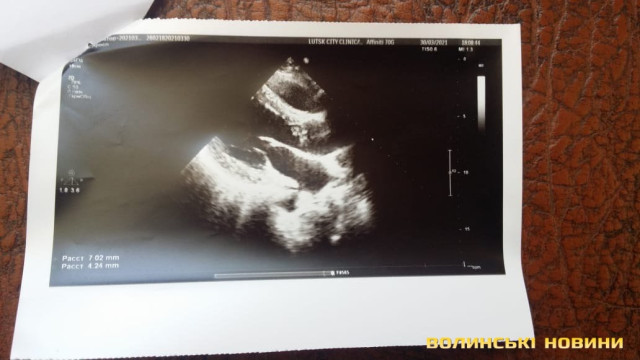

Під час лікування у медзакладі кардіохург поставив автовцю діагноз - первинний інфекційний ендокардит аортального клапана.

Наразі волинянину необхідна операція на серці: треба замінити один із клапанів, що уражений інфекцією, яка може поширитися на здорові тканини. Єдиним правильним рішенням є тільки заміна клапану, інших варіантів лікування, на жаль, немає.